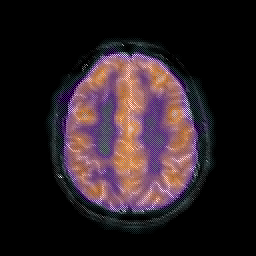

AIDS dementia: overlay -- Slice #13

[Home][Help][Clinical][Tour 1] Slice 13